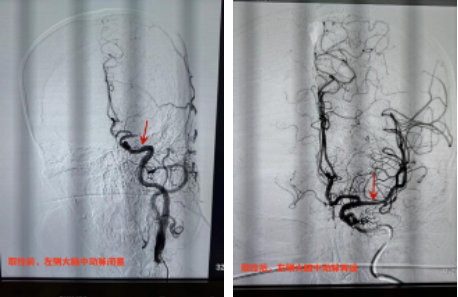

手术台上,卒中中心团队通过微导管及导丝配合,快速而细致地进行着每一步操作。因为每一分钟、每一秒钟对于患者都至关重要,闭塞的血管早开通一秒钟都会多挽救出更多的脑细胞。经过1个多小时的取栓治疗后,抽拉结合一把实现血管再通,堵塞的斑块最终被成功取出,终于可见血流清晰通过。至此,生命的通道被重新开通,患者在手术台上逐渐恢复意识,右侧肢体可自行抬起。